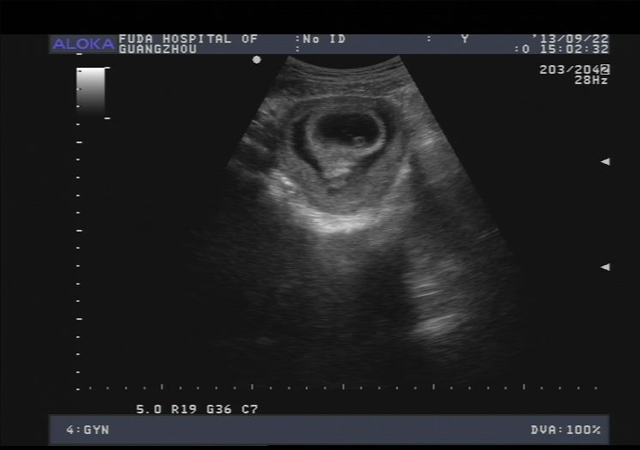

①胎宝宝“走位风骚”,容易出现“女翻男”

做彩的时候,有的宝宝不配合,要么缩个团,要么双腿并的死死的,把分辨男女的最主要特征给挡住,医生护士找了半天看不到男宝宝特征,就会判断是女宝宝。

②脐带造成视觉误差,容易出现“男翻女”

妈妈的子宫空间有限,宝宝跟脐带共处一室,也算是帮宝宝解闷的一个“好室友”了。而有时候脐带所处的位置可能会比较尴尬,看彩超的时候极易让准妈妈和医生错看成男宝宝的生理特征。